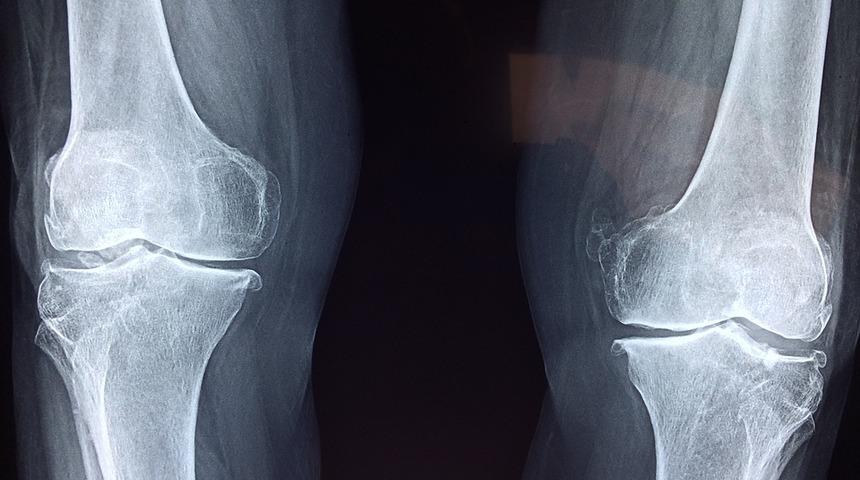

Yeditepe Üniversitesi Kozyatağı Hastanesi Ortopedi ve Travmatoloji Uzmanı Doç. Dr. Turhan Özler, kıkırdak bozulmasıyla orta ve ileri yaşta ortaya çıkan eklem bozukluklarının, ileri teknoloji cerrahi yöntemlerle tedavi edilebildiğini belirtti.

Özler, yaptığı yazılı açıklamada, halk arasında eklem kireçlenmesi olarak da bilinen kıkırdak bozulması sonucu ortaya çıkan rahatsızlıkların, eklem sertleşmesine ve hareket güçlüğüne yol açtığını belirtti.

Hastaların ilk şikayetlerinin hareket kısıtlılığı olduğunu vurgulayan Özler, bireylerin kalça ve diz eklemlerini rahat hareket ettiremediğini, sonrasında buna şiddetli ağrı olabildiğini, zamanla ağrı ve hareket kısıtlılığının, hastanın günlük fonksiyonlarıyla yaşam kalitesini düşürdüğünü anlattı.

Ameliyatların kıkırdağı bozan bazı romatizmal hastalıklar, geçirilmiş travmalar, genetik kaynaklı osteoartrite bağlı olarak diz ve kalça eklemlerinde meydana gelen bozulmalar için uygulanabildiğini aktaran Özler, "Kıkırdak bozulmasıyla orta ve ileri yaşta ortaya çıkan eklem bozuklukları, ileri teknoloji cerrahı yöntemlerle tedavi edilebiliyor. Ciddi sıkıntı ve ağrısı olan bu hastalar, tedavide kullanılan cerrahi yöntemler sayesinde, ağrısız bir yaşam sürdürebiliyor ve bu sayede yaşam kaliteleri de yükseliyor." değerlendirmesinde bulundu.

Doç. Dr. Özler, protez denildiğinde söz konusu materyalin takma bir eklem olduğunun düşünüldüğünü ancak mevcut eklemleri oluşturan kemiklerin üzerindeki bozulmuş kıkırdağın tıraşlanarak, yüzeyinin kaplandığını kaydetti.

Dünya Sağlık Örgütü'nün diz ve kalça eklemi protez ameliyatlarını yüzyılın en başarılı cerrahileri arasında gösterdiğini belirten Özler, şunları kaydetti:

"Diz ya da kalça protezi uygulanan hastalar mutlaka ameliyatın ertesi günü yürütülüyor. Hastalar kuvvetine ve kas gücüne göre değişmekle birlikte ortalama 20 günde sokağa çıkabilecek hale gelebiliyor. Dolayısıyla ameliyat, deneyimli ellerde yapıldığı zaman hem sorun yaşama riski çok düşüyor hem de hastaların yaşam konforu büyük oranda artıyor."